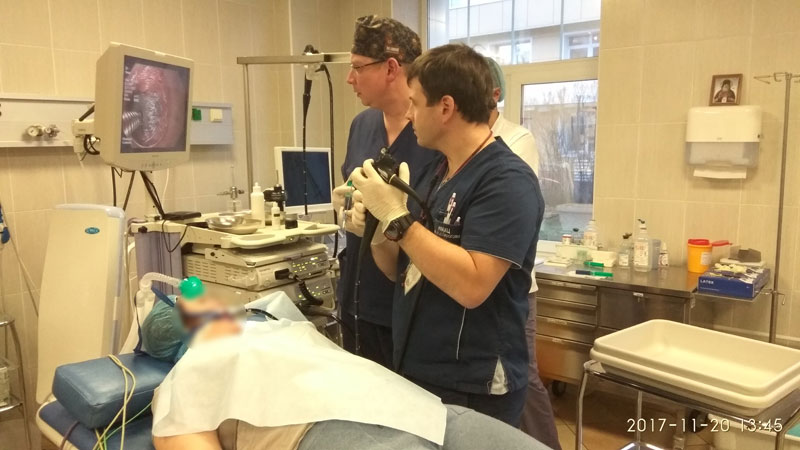

В Пироговском Центре начали проводить трансоральные эндовидеоскопические операции на щитовидной железе.